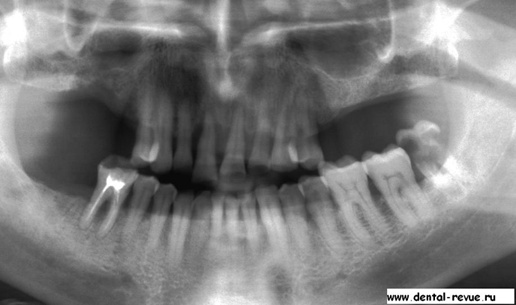

Иллюстрация к книге — Судьба педераста или непридуманные истории из жизни… [i_001.jpg]

Диагностическая ортопантомограмма перед лечением